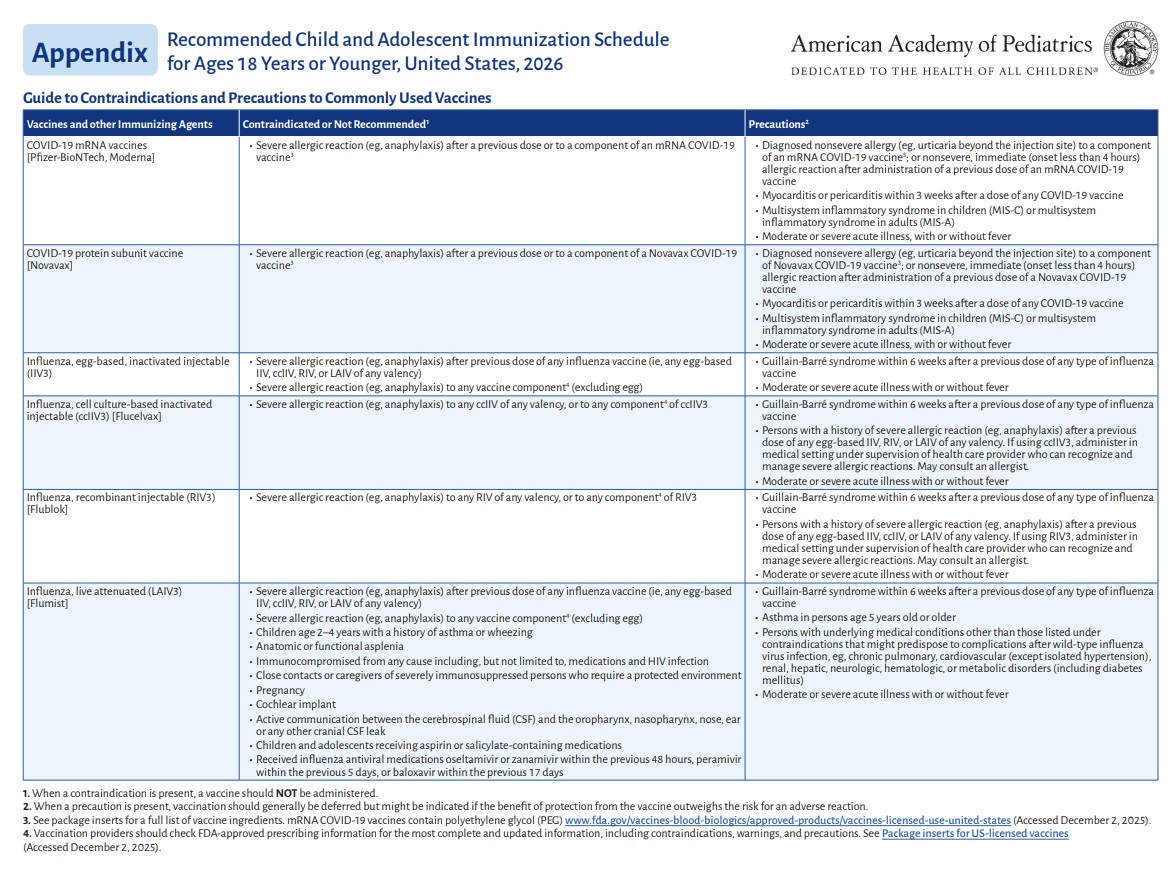

p 5

p 6